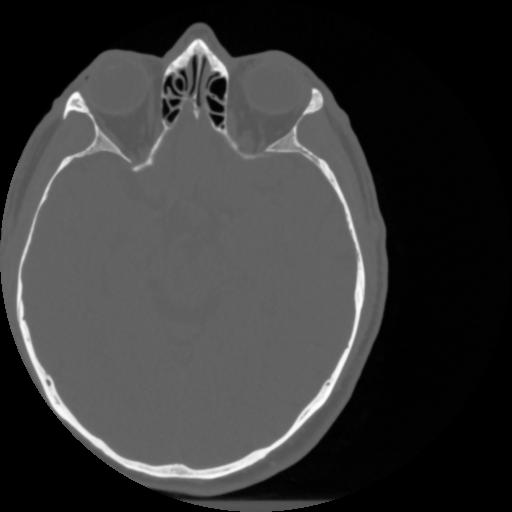

4 CEREBRO,,Vol,0.5,CEREBRO,,